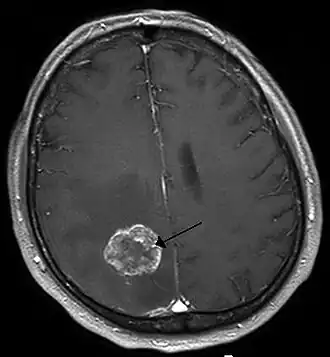

Ressonância magnética de metástases de um cancro do pulmão no hemisfério cerebral direito .